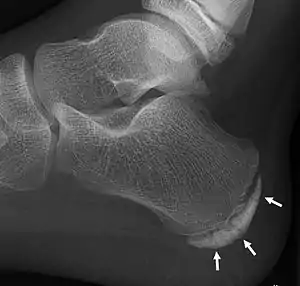

| X-ray of the foot of an 11-year-old child, showing sclerosis and fragmentation of the calcaneal apophysis. This is a sign of low sensitivity and specificity of Sever's disease, because those with Sever's disease may not have it, and this appearance is also present in feet without pain.[1] | |